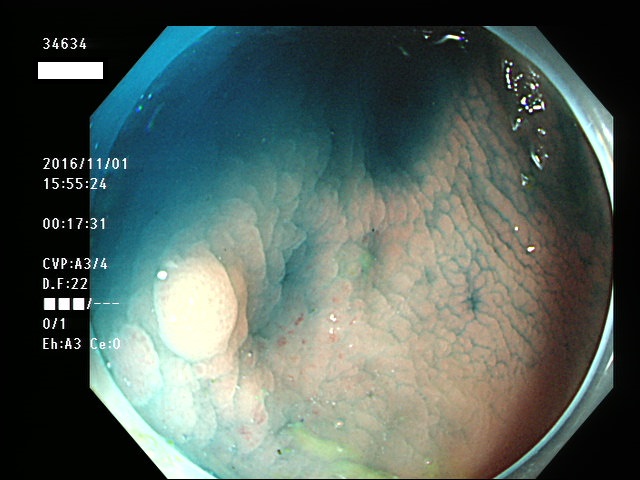

微小カルチノイドの診断

直腸の微小カルチノイドの診断は最も難しい問題です

微小とはいえ、カルチノイドは悪性であり、肛門に近い場所に好発するために、見落とすと数年後には「人工肛門」になる危険があります

進行したカルチノイドの診断は容易なのですが、カルチノイドは「粘膜下腫瘍」と言いまして、は表面が正常粘膜で被われているために微小ですと「単なる過形成結節」「単なる炎症性の隆起」と区別がつかないのです

下記の写真は全て、当院で診断された微小カルチノイド(悪性)ですが、いかに診断が困難かお分かりいただけるでしょう。このような微小病変でさえも見落とせば人工肛門の危険が潜んでいる訳です。